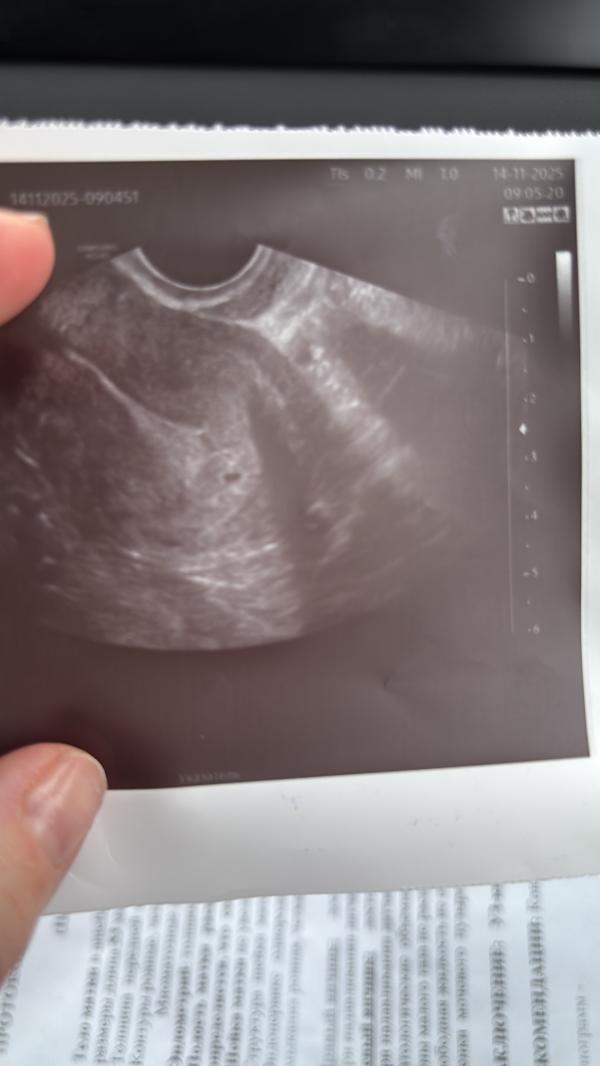

Сегодня была на узи, поставили срок три недели. Врач сказала: мой рабочий день начался с Новой жизни🙏🥹❤️